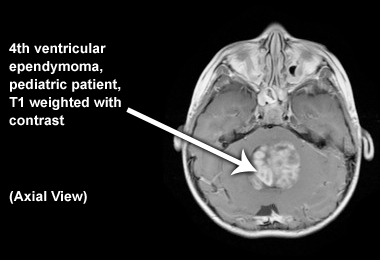

Axial image

Below is an image of fourth ventricular ependymoma in a pediatric patient (T1 weighted with contrast):